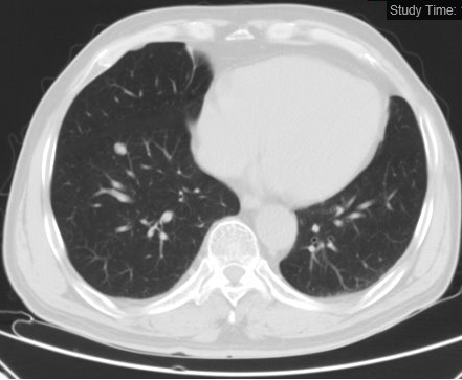

2018.05.02 肺部新增多发小结节,腹部未见肿瘤复发

2018.05.02:

2018.07.20: